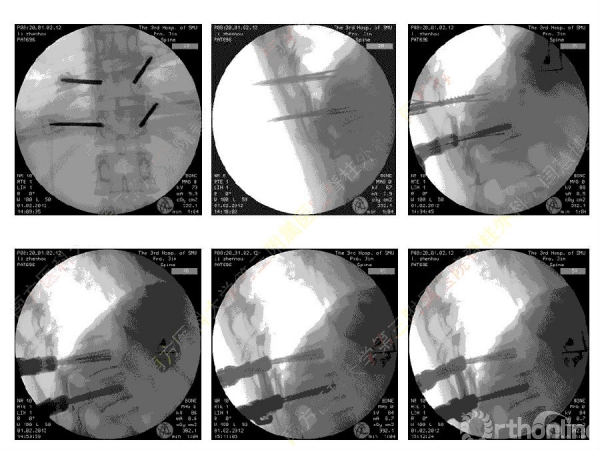

胸腰椎骨折是指由于外力造成胸腰椎骨质连续性的破坏,在如车祸、高处坠落等意外事故中,是最常见的脊柱损伤。老年患者由于本身存在骨质疏松,甚至有可能因为一些如滑倒、跌倒等低暴力因素导致胸腰椎骨折。胸腰椎骨折患者常合并神经功能损伤,且由于致伤因素基本为高能损伤,常合并其他脏器损伤,这为治疗带来了极大的困难和挑战。针对胸腰椎骨折,南方医科大学第三附属医院闫慧博教授介绍了他们运用微创方法治疗的经验。